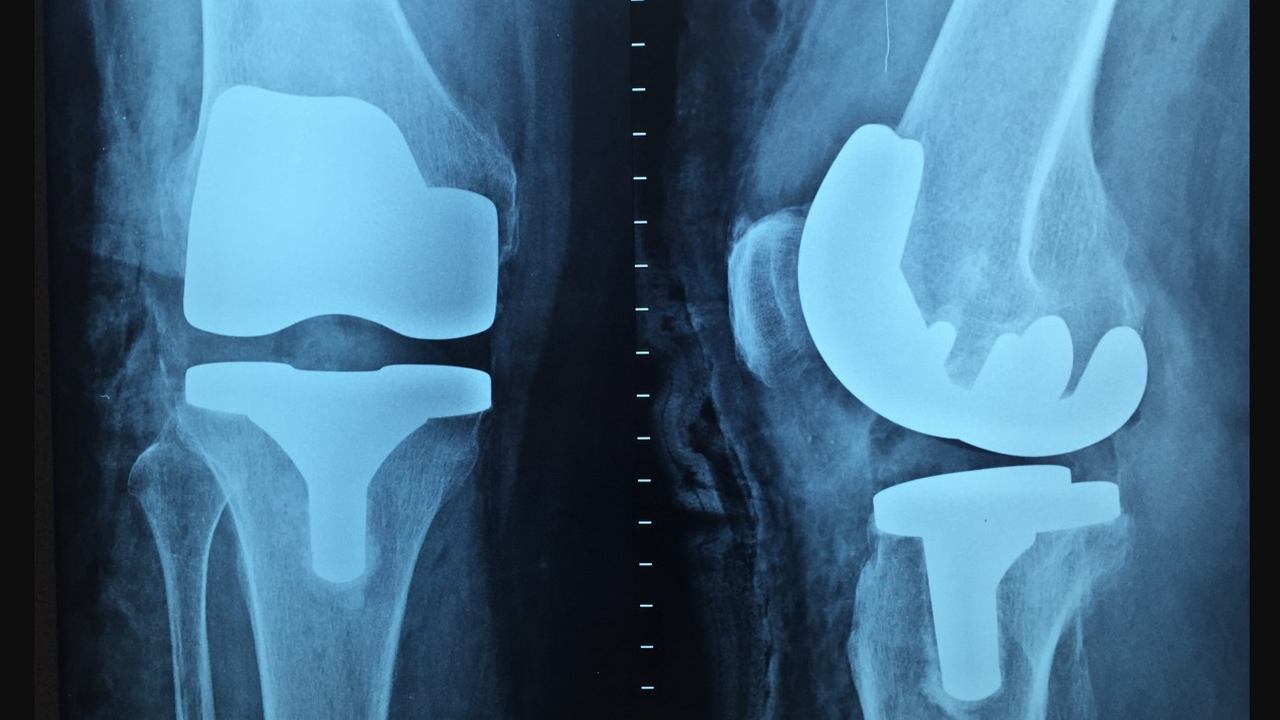

Every year on 20 October, World Osteoporosis Day is celebrated across the world to raise awareness about the disease that severely affects the bone health of an individual. This medical condition is such that it makes a person’s bones weak enough to fracture at the slightest impact. According to statistics, one in every three women over 50 years of age suffer an osteoporotic fracture. One in five men also face the same risk but only around 20 percent of osteoporosis patients are lucky to be diagnosed and treated. History and Significance: The United Kingdom’s National Osteoporosis Society observed World Osteoporosis Day for the first time on 20 October, 1996. This initiative was further supported by the European Commission with a prime aim to prevent fractures caused by osteoporosis. It tried to bring policymakers, professionals, and the common public together in order to raise awareness around osteoporosis and make health a priority. The World Health Organization (WHO), in the late 90’s, began to co-sponsor this day along with International Osteoporosis Foundation (IOF). On this day, the IOF organises various events. The day is marked to raise awareness about the disease, its symptoms, prevention, and treatment. It also educates people about the importance of getting tested on regular basis for the diagnosis of osteoporosis at an early stage. Let’s take a look at the problems Osteoporosis patients can face: - Bone tissues deteriorate in Osteoporosis - Brittle bones can lead to frequent fractures - If osteoporosis begins affecting the spine of a person, it can lead to severe pain and a stooped posture - This condition can also lead to early menopause - Several people are also at risk of developing other conditions along with osteoporosis such as digestive disease, rheumatoid, and diabetes In order to find out if you have Osteoporosis, one needs to undergo a bone mineral density (BMD) test. This test measures the density of a person’s bones with the help of a machine and can be carried out on different bones of an individual’s body be it hip, forearm, wrist, or spine. In case, one is suffering from extreme backache or neck pain and faces difficulties in their body posture, they can undergo a BMD test to check if they have osteoporosis. Here are some exercises to follow if you are diagnosed with osteoporosis: Balancing exercises help a patient to strengthen their legs. Rising up to one’s toes and then going back to their heels is an effective balancing exercise. Posture exercises are important for those who are suffering from stooping shoulders. It also helps in flattening the upper back. Practicing functional exercises such as wall slides can also help in improving the posture of the shoulders. Hip and back strengthening exercises also improve balance.